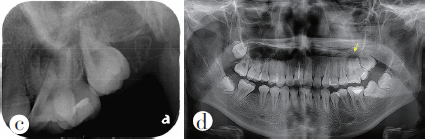

临床检查:67牙冠相连,6牙冠近中倾斜,未见明显牙体病损,叩痛(+),无松动,牙髓电活力测试无反应;7牙冠远中倾斜,面可见充填物,叩痛(+),无松动,牙髓电活力测试无反应,腭侧黏膜可见窦道;67颊侧牙体结合部探及牙周袋深约5mm(图1a~b)。X线根尖片可见67冠根影像交错重叠(图1c);曲面断层片可见67冠部相连,牙根交错(图1d);结合锥形束CT(CBCT)可见67在牙冠颈1/3处融合,6近颊根(MB)可见两根管,远颊根(DB)疑似与7颊根(B)有融合,腭侧可见6腭根(P)及7腭根(P),67根分叉及根尖区可见大面积低密度透射影,腭侧骨壁破坏(图1e~f)。临床诊断:67慢性根尖周炎、融合牙。 医学百科网 | YxBaike.Com

图1a、b治疗前口内像;c治疗前X线根尖片;d治疗前曲面断层片;e、f治疗前CBCT横断面片; 医学百科网 | YxBaike.Com